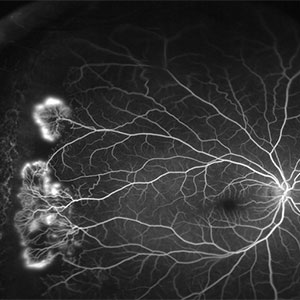

FFA (Fundus Fluorescein Angiography)

This is an invasive test requiring injection of a dye into the arm vein. Pictures are then taken of the retina to study the extent of avascularity, leakage from blood vessels and changes in the retinal pigment epithelium.

This procedure can cause nausea and vomiting in some individuals. A very important side effect is allergic reaction to the dye. There have been instances of severe anaphylactic shock and death following injection of the dye. Though this is a very rare complication, it cannot be ignored.

As most conditions can be diagnosed with a good clinical examination, we avoid this test for this reason, unless it is absolutely required.

At Advanced Retina Care we do not want to put patients in ANY sort of risk. We only perform procedures which are 100% safe for you.